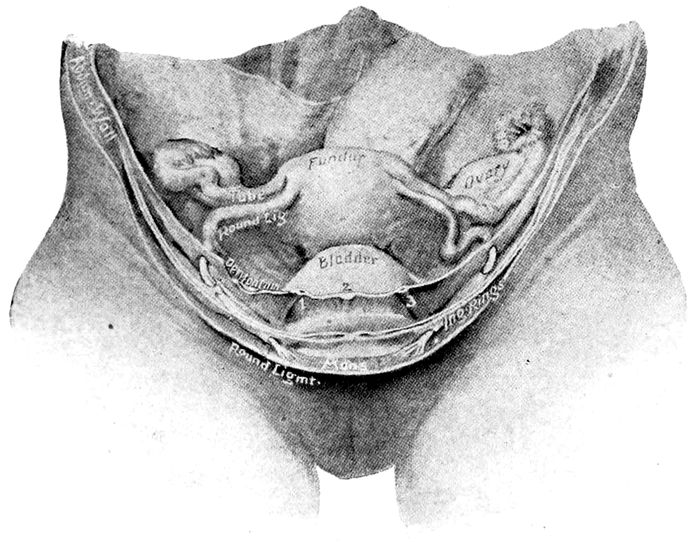

Fig. 3.—Visceral relations. (Redrawn from Gray.)

Fig. 4.—Uterus and appendages. On either side of the uterus will be seen the ovary, the fimbriated extremity of the tube, the tube, and the round ligament. The vagina lies open below. (Lenoir and Tarnier.)